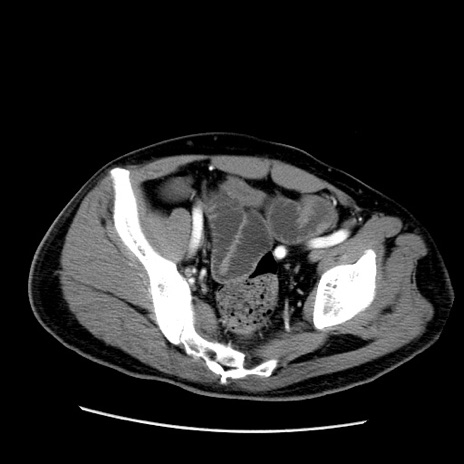

冠状断像

【症例】50歳代男性

【主訴】腹痛

【現病歴】AVMからの被殻出血のため回復期リハ病棟入院中。 本日午後3時頃急に下腹部痛が出現した。

【既往歴】AVM、被殻出血、虫垂炎、高血圧

【身体所見】意識晴明、左半身不全麻痺、会話の理解は良好、36.5°C、腹部:膨隆、全体に板状硬、下腹部正中に圧痛点あり、反跳痛-、筋性防御不明、右下腹部にope scar

【データ】WBC 9400、CRP 0.06